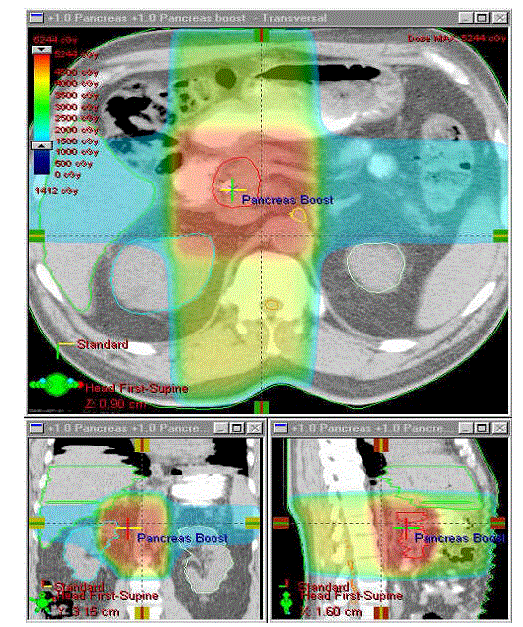

Figure 1. Three-dimensional treatment plan with color wash dose-distributions identifying dose delivered to tumor volume and surrounding normal anatomical structures.